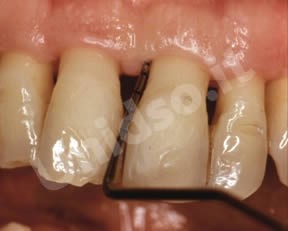

L’ Unità Operativa di Parodontologia e Igiene Orale si compone di 5 sezioni. L’attività’ clinico-assistenziale è svolta da diversi odontoiatri, supportata da igienisti dentali e assistenti alla poltrona, ed è articolata sulla base di appuntamenti programmati. Nell’Unità Operativa di Paradontologia e Igiene Orale del DSMOB si eseguono le seguenti prestazioni odontoiatriche: istruzioni d’igiene orale, ablazione tartaro, full radiografico, terapia dell’alitosi, levigatura radicolare, chirurgia parodontale riparativa, resettiva e rigenerativa e chirurgia plastica dei tessuti molli parodontali.